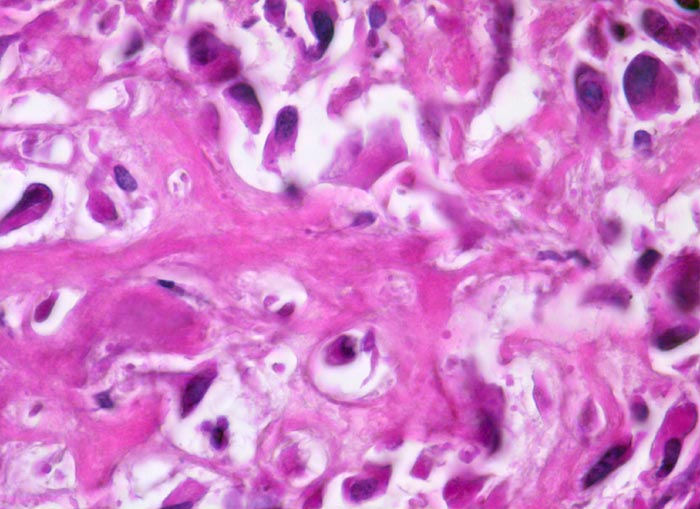

Osteosarkom

Netz aus schmalem, verzweigtem, teils verkalktem, neugebildetem Tumorosteoid, das direkt von stark polymorphen mesenchymalen Tumorzellen mit hyperchromatischen Kernen gebildet wird. Die Zytomorphologie ist nach Entkalkung nur eingeschränkt beurteilbar.

Der Nachweis von Osteoid, das von atypischen Zellen gebildet wird, ist das wichtigste Kriterium für die Diagnose eines Osteosarkoms. Osteosarkome können aber auch auf weiten Strecken ausschliesslich chondroide oder fibröse Matrix bilden und dann ein Fibrosarkom, Chondrosarkom oder ein malignes fibröses Histiozytom imitieren.

Histologie

630